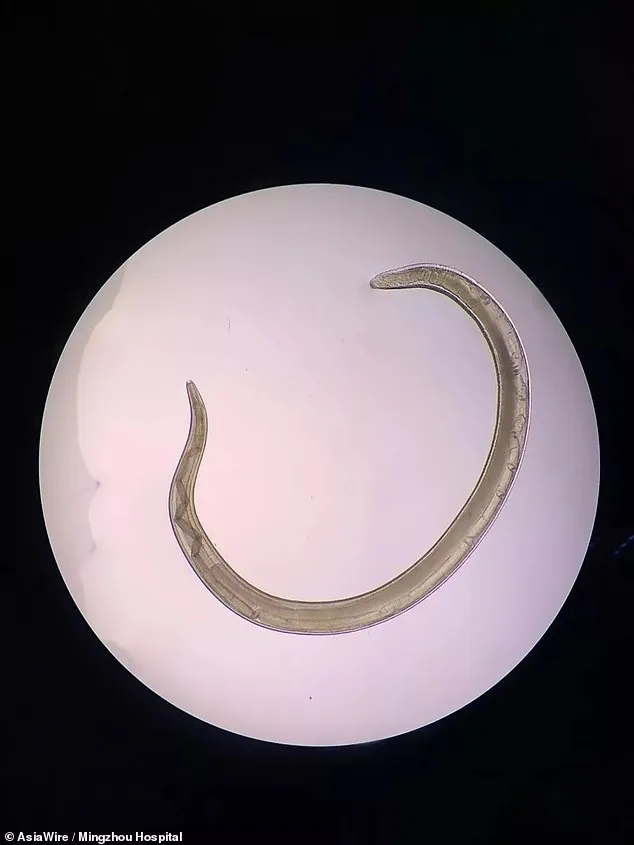

ด้านดร. โจว กูปิง เปิดเผยว่า ปรสิตที่พบในดวงตาของนายหยานนั้นถูกเรียกว่า Thelazia callipaeda หรือ หนอนพยาธิตา มีความยาวประมาณ 2 ซม. (0.8 นิ้ว) มีลักษณะสีขาว คล้ายเส้นด้ายขนาดเล็ก เคลื่อนไหวได้ เมื่อเข้าสู่ดวงตาจะทำให้เกิดการอักเสบและในกรณีที่รุนแรงสามารถทำลายกระจกตา ซึ่งอาจนำไปสู่การมองเห็นที่บกพร่องได้

สำหรับ หนอนพยาธิ Thelazia callipaeda หรือ หนอนพยาธิตา ที่พบในดวงตาของนายหยานนั้น แพทย์เชื่อว่าน่าจะแพร่กระจายมาจากสุนัขของนายหยาน เนื่องจากพยาธิสายพันธุ์นี้มักพบในแมวและสุนัข ซึ่งนอกจากจะพบว่ามีพยาธิแล้วแพทย์ยังพบไข่ของพยาธิอีกหลายฟองด้วย